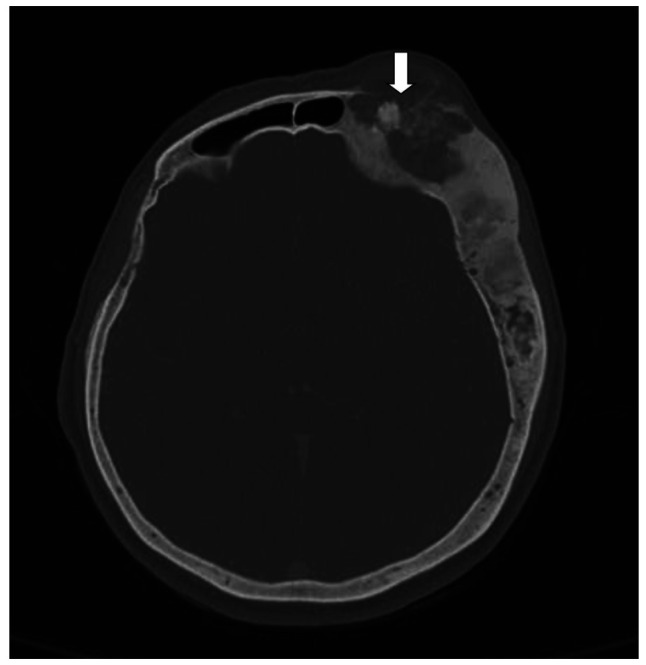

纤维性发育不良是一种良性纤维骨性病变,很少发生恶性转化,通常在放射治疗后发生。骨肉瘤是纤维结构不良中最常见的恶性肿瘤。我们报告一例67岁的女性患者骨肉瘤发展为长期纤维性发育不良没有事先放疗。患者接受手术和术后化疗。在最初的治疗后的四年中,她出现了两次复发。在这种情况下,我们想强调注意纤维发育不良患者在其他方面不显著的病程中任何显著变化的重要性。

Fibrous dysplasia is a benign fibro-osseous lesion which rarely undergoes malignant transformation, frequently after radiotherapy. Osteosarcoma is the most common malignancy arising in fibrous dysplasia. We report a case of 67-year-old female patient with osteosarcoma developing in long lasting fibrous dysplasia without prior radiation. The patient underwent surgery with postoperative chemotherapy. She developed two relapses over the course of four years after the initial therapy. With this case, we want to underline the importance of noticing any significant change in the otherwise unremarkable course in patients with fibrous dysplasia.